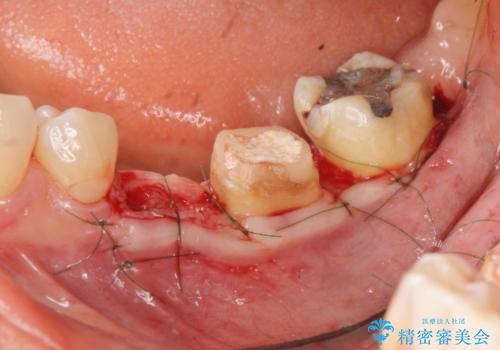

- 大人になってからも残っていた乳歯が揺れ始め、抜歯を覚悟しインプラント治療を希望して来院されました。

X線写真より、乳歯は抜歯が必要な状態でインプラントは小臼歯の埋伏により難しい状況であったのでブリッジによる補綴を選択しました。

ブリッジ治療の予知性を高めるために、虫歯の徹底的な除去に加え縁上歯質を確保するための歯周外科手術、マイクロスコープを用いた精密根管治療を行う治療計画としました。